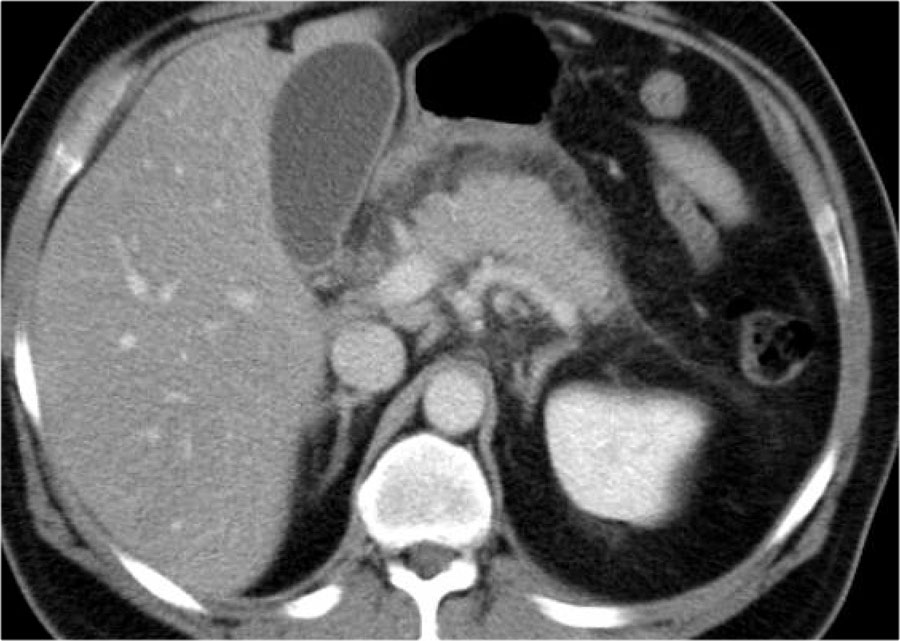

Đây là một trường hợp khác của viêm tụy thể kẽ không có hoại tử.

Cuộn qua các hình ảnh để xem.

Tụy phù nề và có viêm quanh tụy (2 điểm).

Không có ổ dịch.

Không có hoại tử tụy.

CTSI: 2 điểm